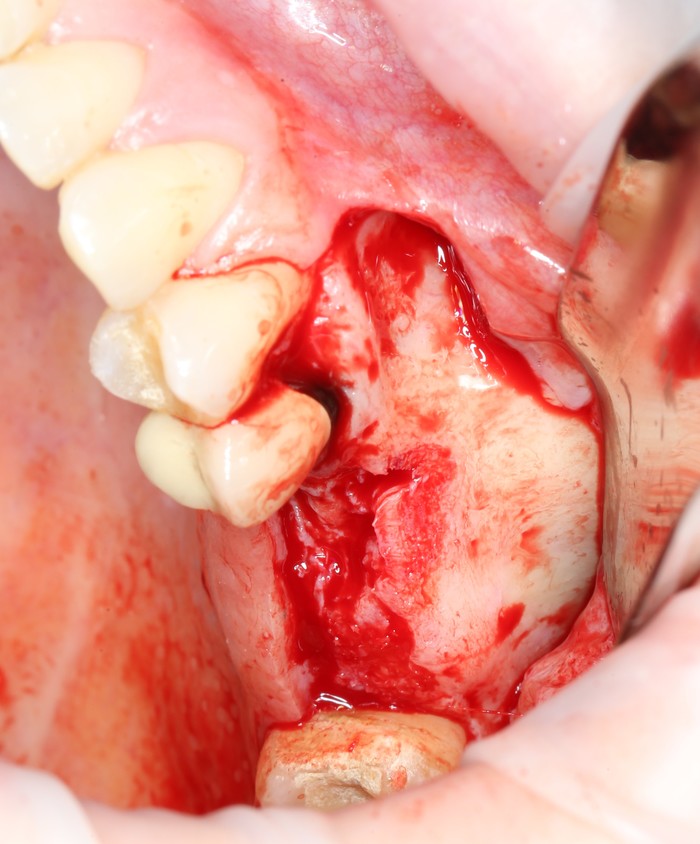

Мной и ортопедом было принято решение по удалению пятого зуба, потому как перелечить его будет, к сожалению, невозможно.

Удаления зубов, как правило, проводится при помощи специального инструмента – элеватора, а не щипцов, как многие думают.

Конечно, щипцы тоже используются, но зачастую, можно обойтись и без них.

«Вжух»:

Лунка моментально заполняется кровяным сгустком.